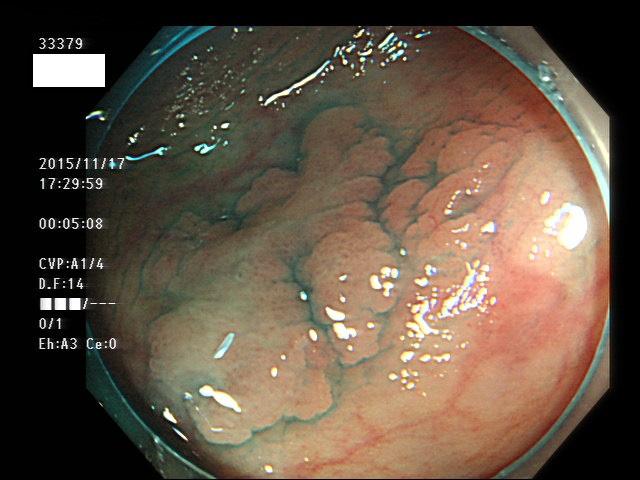

上記100名より抽出した平坦・陥凹型腺腫(=癌化の危険が高いが見落としやすい病変)の内視鏡写真